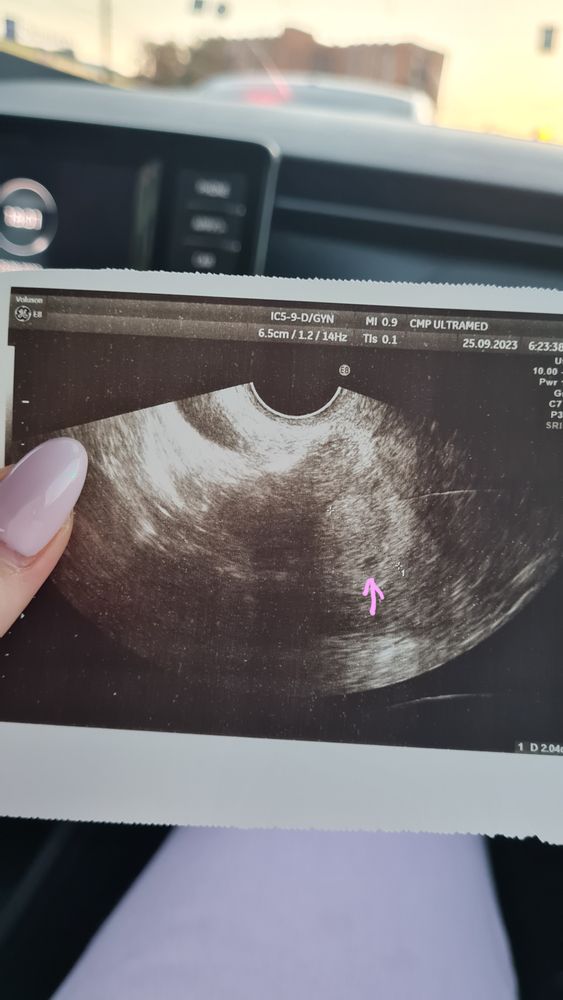

ПЯ 2 мм на 5 д.з. и 19 дпо🌸

Девочки, начитавшись на форуме, что плодное яйцо видно при ХГЧ от 1000, получив результат 1250, зачем-то на 5ый день задержки и 19 дпо поперлась вчера на узи🤦♀️ Овуляция была на 18-19 дц. В итоге в матке увидели маленькое ПЯ 2 мм, сказали, еще рано. Теперь накручиваю себя, что оно такое маленькое.😒Подскажите, у кого-нибудь находили ПЯ такого маленького размера при ХГЧ больше 1000 и дальше всё было хорошо с Б?🙏

Нормальное мы для такого ХГЧ и срока

При ХГЧ 1900 пя было 3 мм